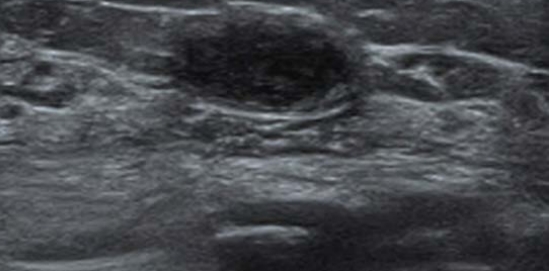

矽膠饅化的超音波影像

.jpg)

跟玻尿酸饅化的黑色水潭(無回音區)影像不同, 矽膠會呈現出一片邊界不清、亮白色(高回音)的雜訊,就像散沙一樣滲透在組織間隙中,這也是為什麼矽膠難以完全取出的原因。

矽膠饅化的處理只有一條路:取出。 手術把它夾出來時,往往真的能看到亮晶晶、帶顆粒感的固態物質,與玻尿酸或脂肪那種「軟組織感」完全不同。雖然相對麻煩,但取出後大多能恢復自然的外觀。